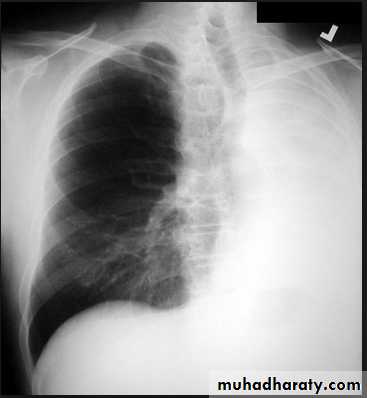

Pleural Effusion on Chest Radiographs.

Posteroanterior (A) and lateral (B) chest radiographs demonstrate the typical meniscoid appearance (arrows) in a patient with a left pleural effusion